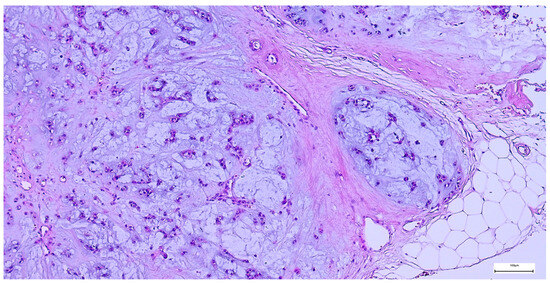

Basal cell adenoma was identified in nine cases, all cases presenting as unilateral, rounded-ovoid, small-sized, encapsulated nodules, with a mean of 24.44 ± 9.82 mm. The lesions displayed variable histological patterns, along with cyst formation in three cases, the tumor cells being associated with a fibrocellular stroma (Figure 16). Complete excision was achieved in eight cases (88.89%), following SP in most cases (Table 3). IHC was performed in five cases (55.6%), highlighting the tumor cell population dual epithelial (AE1/AE3, CK7, and CD117 positive expression) and myoepithelial (p63, S100, and SMA positive expression) phenotype. AR was negative, and the Ki-67 proliferation index was ≤2% in all assessed cases.

Figure 16. Basal cell adenoma composed of uniform basaloid cells arranged in a solid pattern, associated with a fibrocellular stroma (H&E staining, 10×).